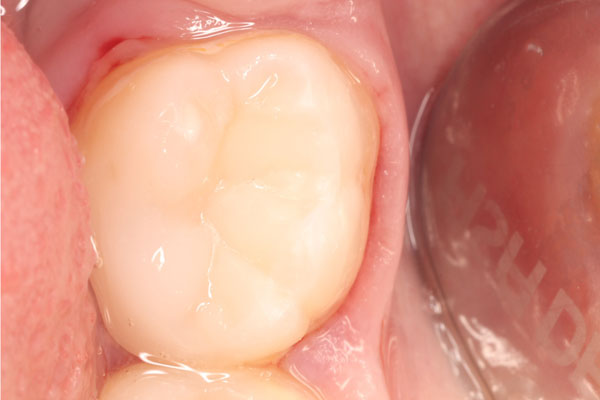

Наши работы